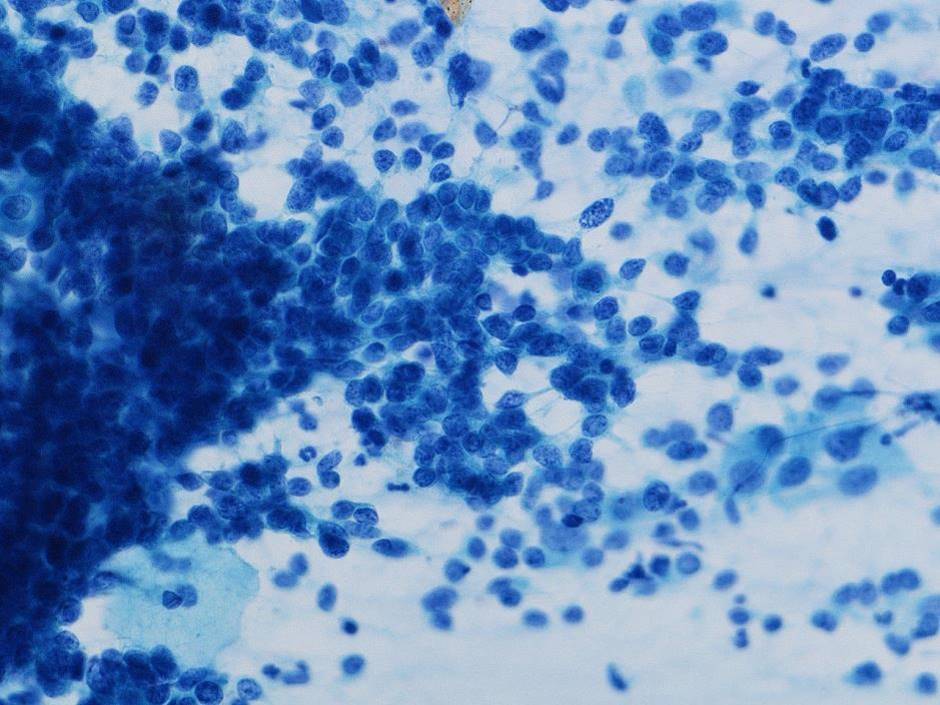

細胞診所見

背景に壊死物質は認められなかった。その中に偏在性核で核クロマチン増量を示す腺系異型細胞の不整形集塊を認めた。柵状配列や腺管構造もみられ上皮内腺癌を疑う細胞と考えた。またN/C比が高く細顆粒状の核クロマチンを有する傍基底型核異常を疑う細胞もみられた